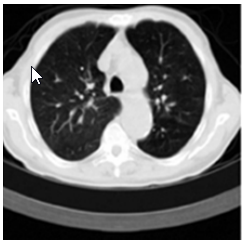

ภาพที่ 2 ตัวอย่างผลการถ่ายภาพปอดด้วยวิธีการ เอกซเรย์ (X-Ray)

ที่มา José Silvestre Silva, Augusto Silva, and Beatriz Sousa Santos. (2000) , http://eprints.utcc.ac.th/2760/3/2760fulltext.pdf

ข้อมูลภาพที่ได้จากการนำไปประมวลผลนั้นก็สามารถนำไปใช้ประโยชน์ในด้านต่าง ๆ ด้วยแพทย์สามารถตรวจดูอวัยวะภายในร่างกายของมนุษย์เพื่อใช้ในการวินิจฉัยโรค ซึ่งเป็นการถ่ายภาพโครงสร้างอวัยวะภายในร่างกายของมนุษย์ ซึ่งเราเรียกว่า เอกซเรย์ (X-Ray) มาจนถึง CT Scan (Computed Tomography) ที่มีความสามารถถ่ายภาพและแสดงภาพในแนวตัดขวางได้ ซึ่งมีประโยชน์มากในการตรวจการรักษาจากผลลัพธ์ของภาพที่มีความละเอียดและชัดเจนมากขึ้น

ในด้านเทคนิคเพื่อทำให้เกิดภาพที่ชัดและสมบูรณ์มากขึ้นโดยวิธีการซ้อนทับภาพ (Image Registration) โดยส่วนใหญ่ใช้เพื่อติดตามความผิดปกติที่เปลี่ยนแปลงไปของอวัยวะ โดยเมื่อนำภาพเก่าก่อนการสังเกตมารวมกับภาพภายหลังการสังเกต ซึ่งจะมองเห็นการเปลี่ยนแปลง หรือความชัดเจนของความผิดปกติ นั้น ๆ เมื่อพูดถึงผลของภาพของการทำเอกซเรย์ที่นำเสนอไปก่อนแล้วนั้น เทคนิคการหาขอบเขตภาพ (Image EdgDeTection) ถือเป็นเทคนิคสำคัญที่ทำให้การวินิจฉัยของโรคมีประสิทธิภาพ ยกตัวอย่างการหาขอบเขตของปอด ที่อยู่บริเวณทรวงอกและการกำจัดสัญญาณรบกวนออกจากภาพ (Image Filters)